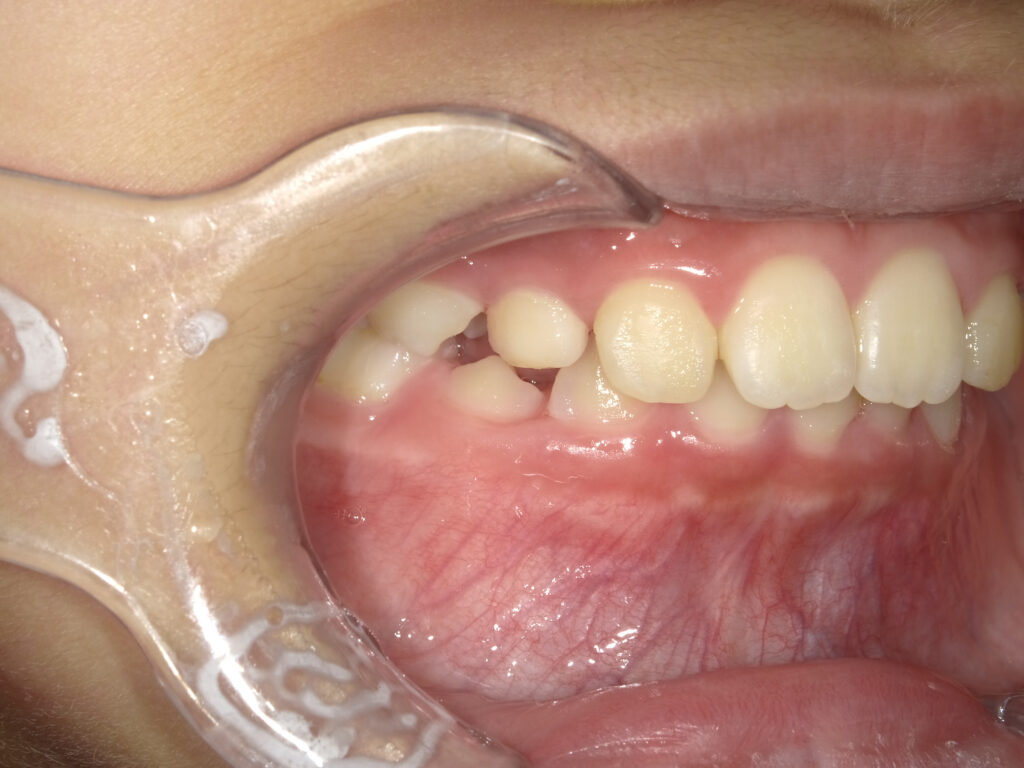

左側

治療前